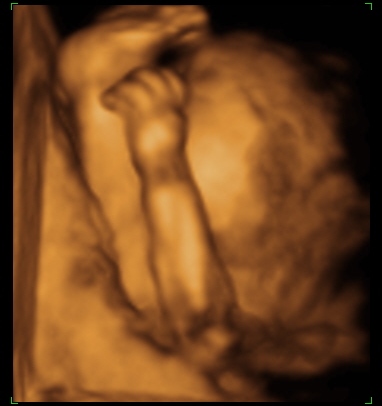

Megjártuk tegnap a 4d-t. Igazatok volt.Szuper volt látni a kis Törrpét. Az ujjacskáit, lábiját, kis pofit. Párom szerint már most is látni, hogy a nózit tőle örökölte. :D

Megpróbálok pár képet feltenni. Kép Tornászbajnok Kép Szundi Kép Szundi méhlepényes takaróval

Teljesen meghatódtam a képektől!!! :D Mi lesz akkor velem holnap?Jaj,olyan nagyon várom már!Nagyon édes a kisbabád! :D

Nagyon jók a képek! Most irigykedem, hogy a Te babód milyen tisztán látszik! :D Nagyon aranyos!!!

Annyira édes a babód! :D Már én is nagyon szeretném látni Pöttyöt. De úgy tervezzük, hogy csak a 26. héten megyünk. Jajj! Az még egy hónap.

Nyerkit: csodálatosak a képek. Tudom a dvd-n még nagyobb élmény.